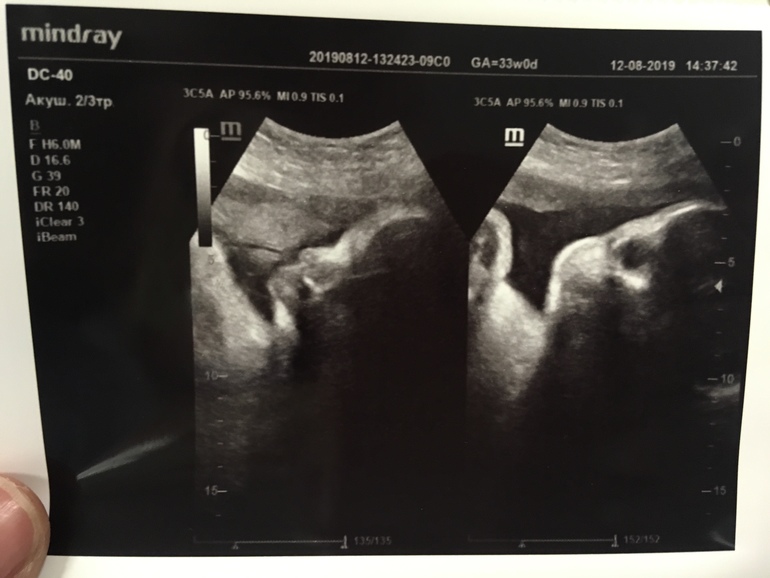

А это моя прекрасная девочка. 🥰

Малышка опережает. Вес и рост на 34 полных недели (сейчас 33 ровно). Ввиду чего мой ПДР сместился с 5 октября на 24 сентября. Учитывая тот факт, что сына я родила раньше ПДР на 8 дней, готовится ко встрече начну числа с 10-го (просебя загадала 15 или 25 сентября. Увидим 🤨🙃).